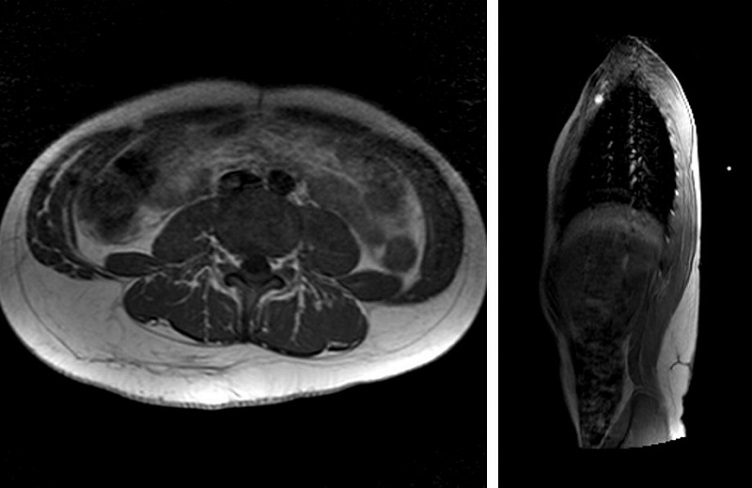

Lactante mujer de 2 meses, antecedente de arteria umbilical única y ptosis palpebral derecha, consultó por hemihipertrofia de pierna derecha y tumoración lumbar derecha. Mediante ecografía se observó un aumento del tejido celular subcutáneo de bordes imprecisos de 4 cm, con aumento progresivo a los 8 meses. A los 12 meses medía 8 x 5 x 3 cm, extendiéndose hacia el glúteo (Figura 1). Estudios cromosómico y genético normales, no encontrándose relación con ningún síndrome asociado SCAL.

La lesión fue extirpada al año y 10 meses. Diagnóstico histológico: lipoma. Se realizaron controles anuales y a los 4 años se evidenció recidiva. A los 9 años se realizó resonancia magnética por crecimiento progresivo (Figura 2), alcanzando dimensiones de >20 cm, generando problemas físicos y estéticos. Se extirpó y se obtuvieron 3 fragmentos lipomatosos, el mayor de 17 x 15 x 3,5 cm, los otros de 4,5 x 2 cm y 2,5 x 1,5 cm, pesando en conjunto 400 g. Sin signos histológicos de malignidad.